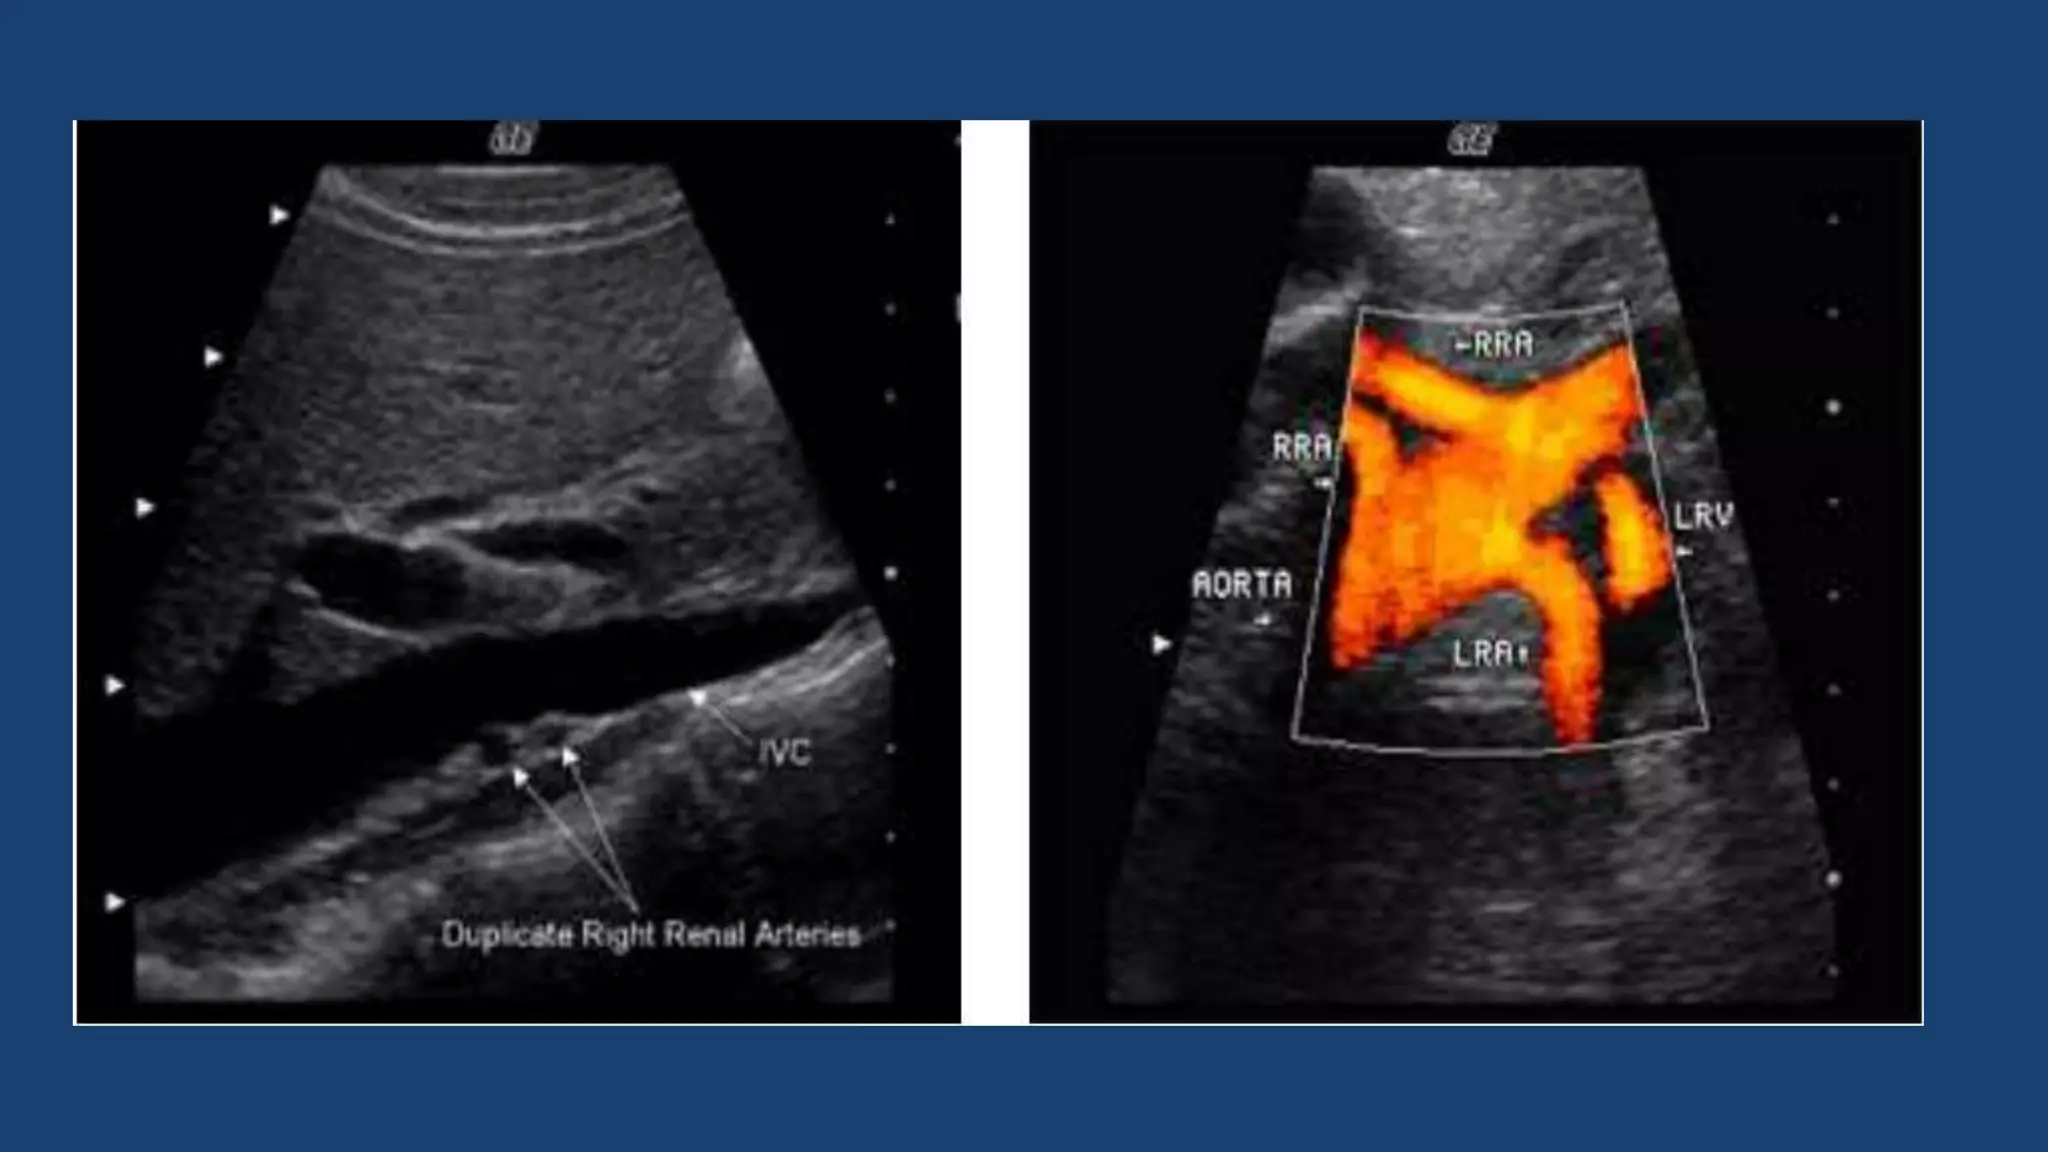

 Variant anatomy is common in the renal vascular system. Approximately 30% of

individuals have more than a single renal artery on each side. Supernumery

arteries may occur unilaterally or bilaterally.

Supernumary right renal arteries.

Supernumerary (duplicate) arteries can be seen looking posterior to

the IVC in B Mode and Color in a sagittal plane.

 Variant anatomyis common in the renal vascular system. Approximately 30% of individuals have more than a single renal artery on each side. Supernumery arteries may occur unilaterally or bilaterally.  Most accessory renal arteries arise from the abdominal aorta, but they may also originate from the common iliac, superior or inferior mesenteric, adrenal, and right hepatic arteries. Supernumary right renal arteries.

ANTERIOR APPROACH The renalarteries are clearly imaged in B Mode from an anterior, subcostal approach however as it is perpendicular to the ultrasound beam it is not suitable for Doppler assessment. Supernumerary (duplicate) arteries can be seen looking posterior to the IVC in B Mode and Color in a sagittal plane. In most cases the anterior approach is used to evaluate the main RAs. APPROACH